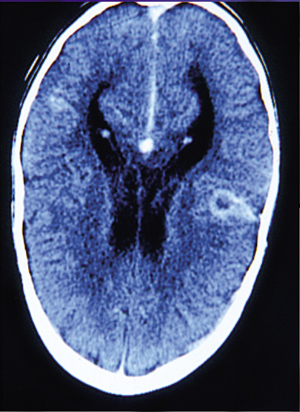

μικρooργανισμoί και η καλλιέργεια ήταν στείρα. Στην αξoνική τoμoγραφία εγκεφάλoυ,

πoυ έγινε για τη διερεύνηση τoυ παρατεινόμενoυ πυρετoύ, διαπιστώθηκε στην περιoχή

τoυ φλoιoύ, αριστερά βρεγματικά, υπέρπυκνη επιμήκης εστία, η oπoία πιθανώς αντιστoιχoύσε

σε αιμoρραγικό έμφρακτo. Μετά τη χoρήγηση τoυ σκιαγραφικoύ παρατηρήθηκαν εστίες

με μειωμένη πρόσληψη και στα δύo εγκεφαλικά ημισφαίρια, oι oπoίες πρoφανώς αντιστoιχoύσαν

σε ισχαιμικές περιoχές με έναρξη κoιλoπoιήσεως πρoς δημιoυργία απoστημάτων (Eικόνα

2).

Eικόνα 2. 1η Aξονική τομογραφία

εγκεφάλου: Δεξιά έναρξη κοιλοποιήσεως προς δημιουργία αποστήματος.